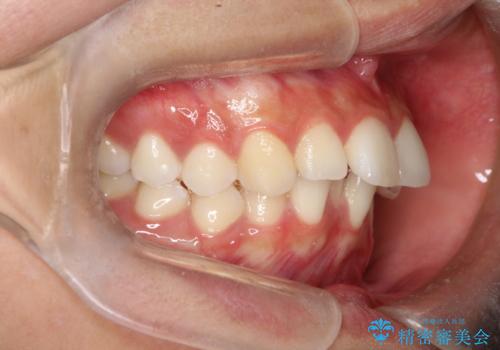

1. 【審美ワイヤー】口元を下げたいの治療前

2. 【審美ワイヤー】口元を下げたいの治療中